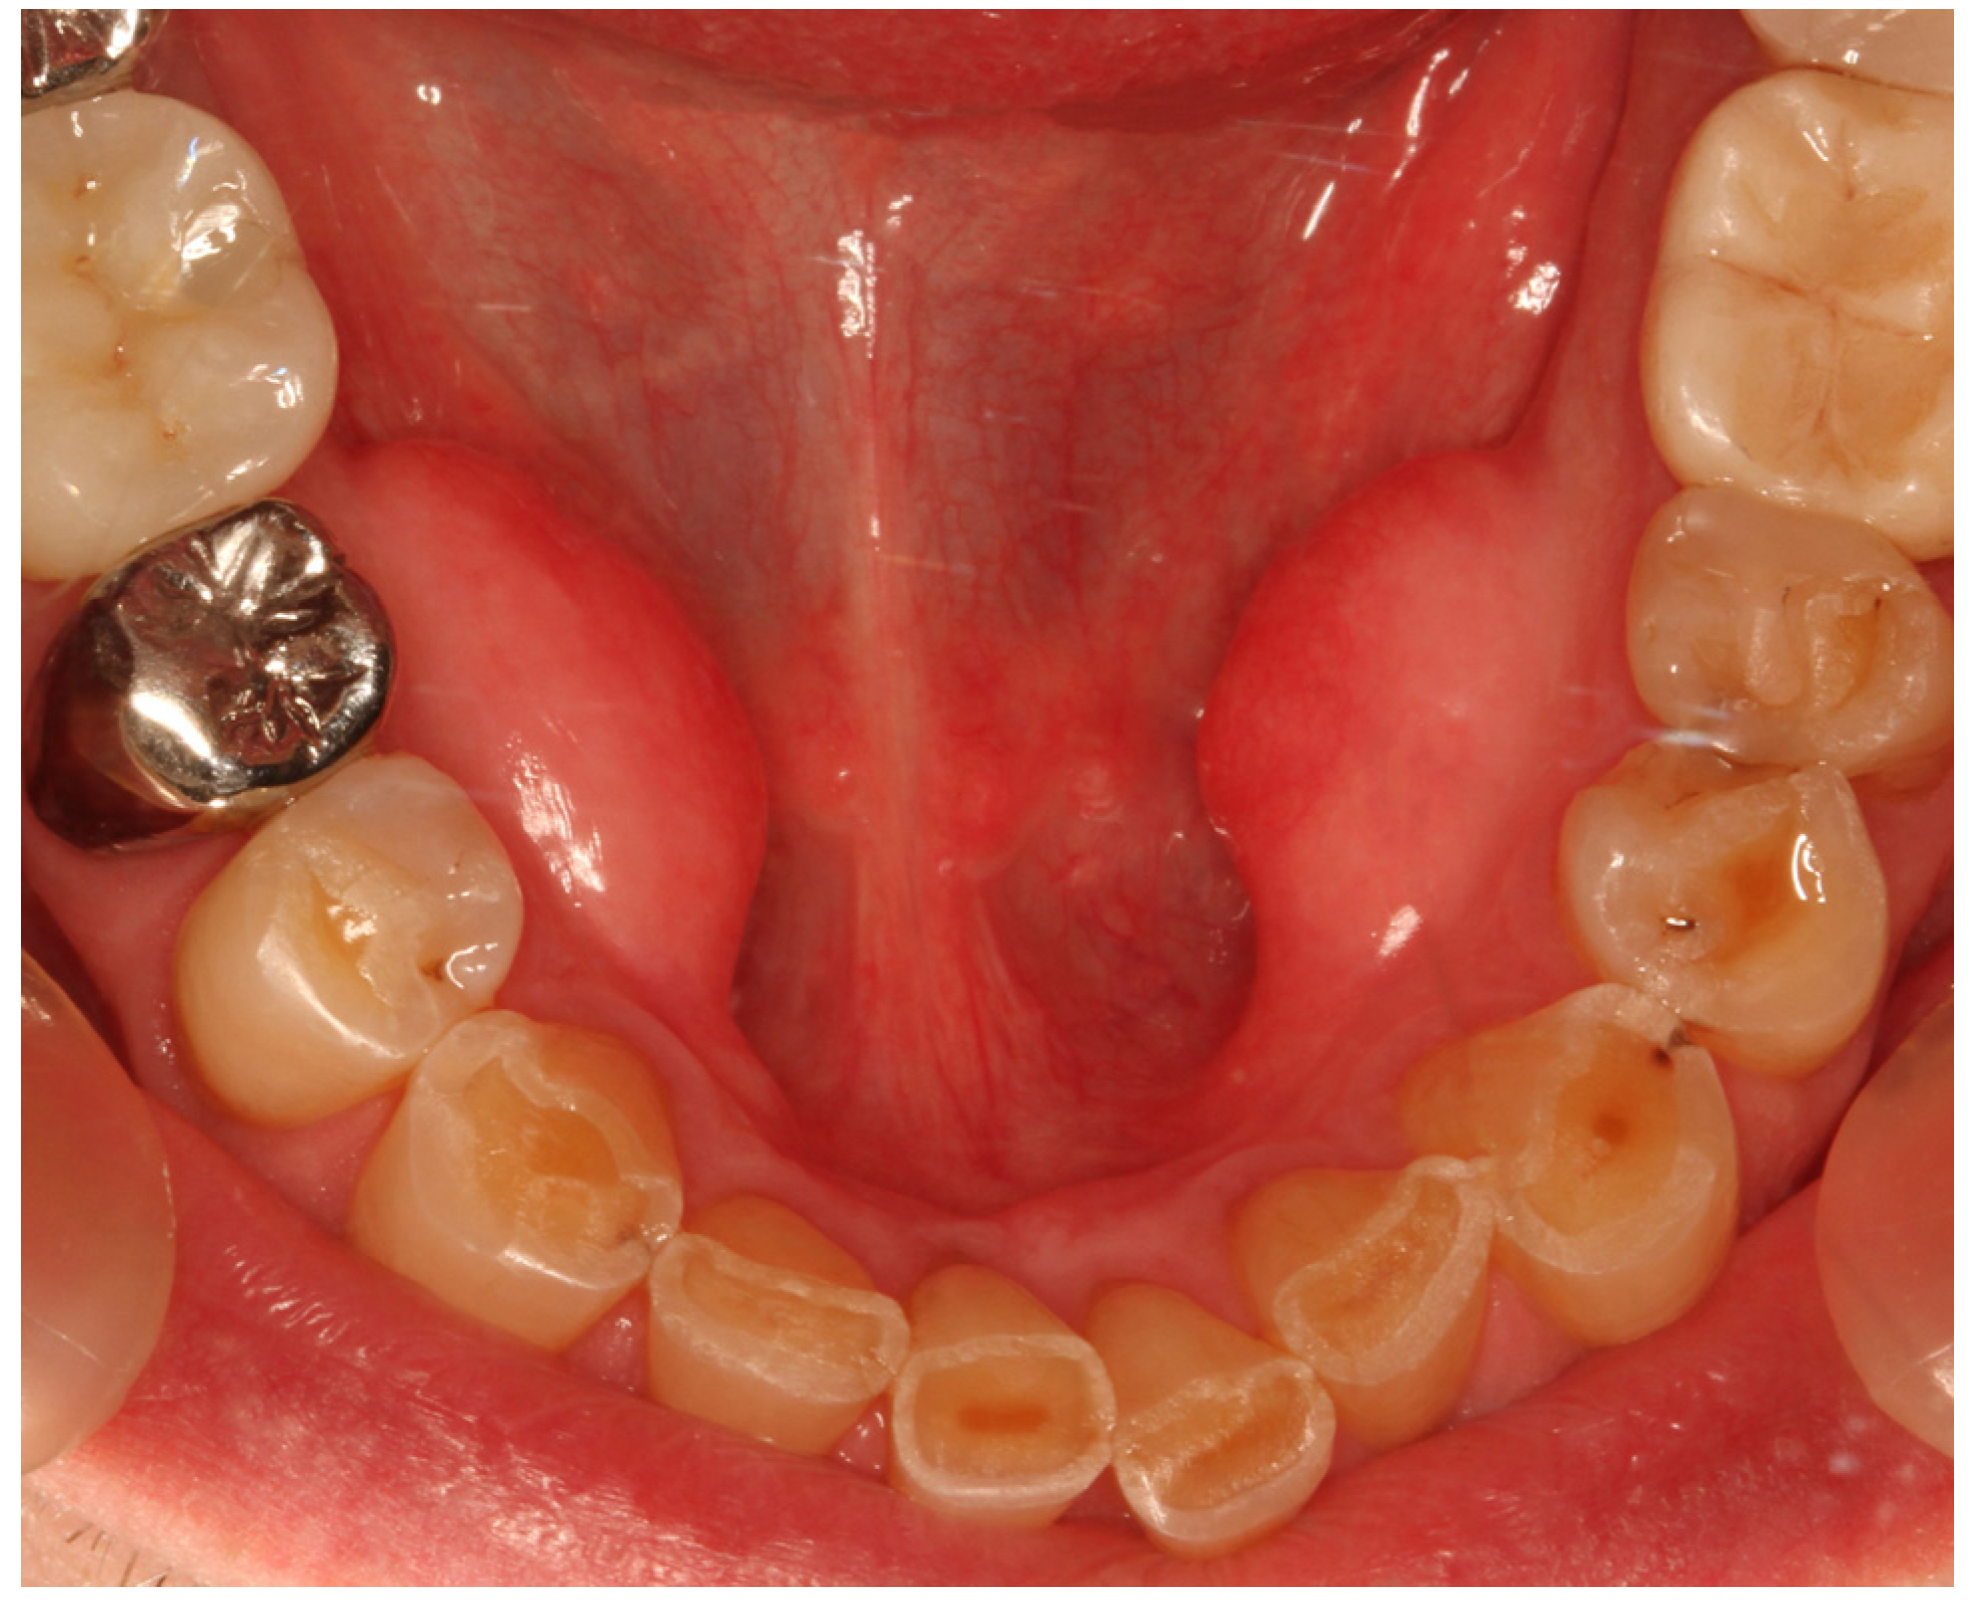

Torus mandibularis (TM) is a frequently occurring, benign bone bulge (exostosis) on the lingual surface of the mandible [1], usually located bilaterally, between the canines and molars and superior to the mylohyoid line (Figure 1) [2].

Figure 1. Patient with bilateral torus mandibularis; male, 47 years old.